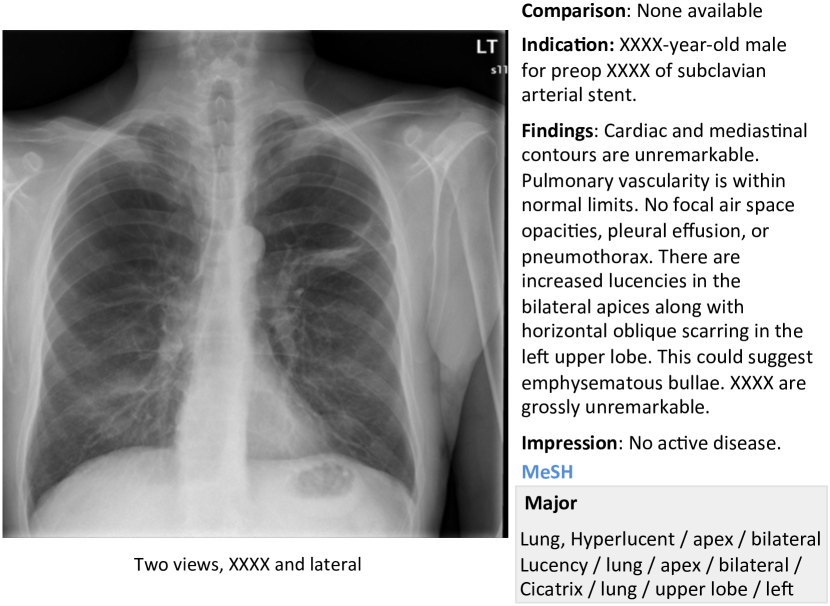

In this work, we demonstrate how to automatically annotate chest x-rays with diseases along with describing the contexts of a disease, e.g., location, severity, and the affected organs. A publicly available radiology dataset is exploited which contains chest x-ray images and reports published on the Web as a part of the OpenI [2] open source literature and biomedical image collections. An example of a chest x-ray image, report, and annotations available on OpenI is shown in Figure 1.

We use a publicly available radiology dataset of chest x-rays and reports that is a subset of the OpenI [2] open source literature and biomedical image collections. It contains 3,955 radiology reports from the Indiana Network for Patient Care, and 7,470 associated chest x-rays from the hospitals’ picture archiving systems. The entire dataset has been fully anonymized via an aggressive anonymization scheme, which achieved 100% precision in de-identification. However, a few findings have been rendered uninterpretable. More details about the dataset and the anonymization procedure can be found in [11], and an example case of the dataset is shown in Figure 1.

Each report is structured as comparison, indication, findings, and impression sections, in line with a common radiology reporting format for diagnostic chest x-rays. In the example shown in Figure 1, we observe an error resulting from the aggressive automated de-identification scheme. A word possibly indicating a disease was falsely detected as a personal information, and was thereby “anonymized” as “XXXX”. While radiology reports contain comprehensive information about the image and the patient, they may also contain information that cannot be inferred from the image content. For instance, in the example shown in Figure 1, it is probably impossible to determine that the image is of a Burmese male.

More examples of chest x-ray image, report, and annotations available on OpenI [2] is shown in Figure 7.